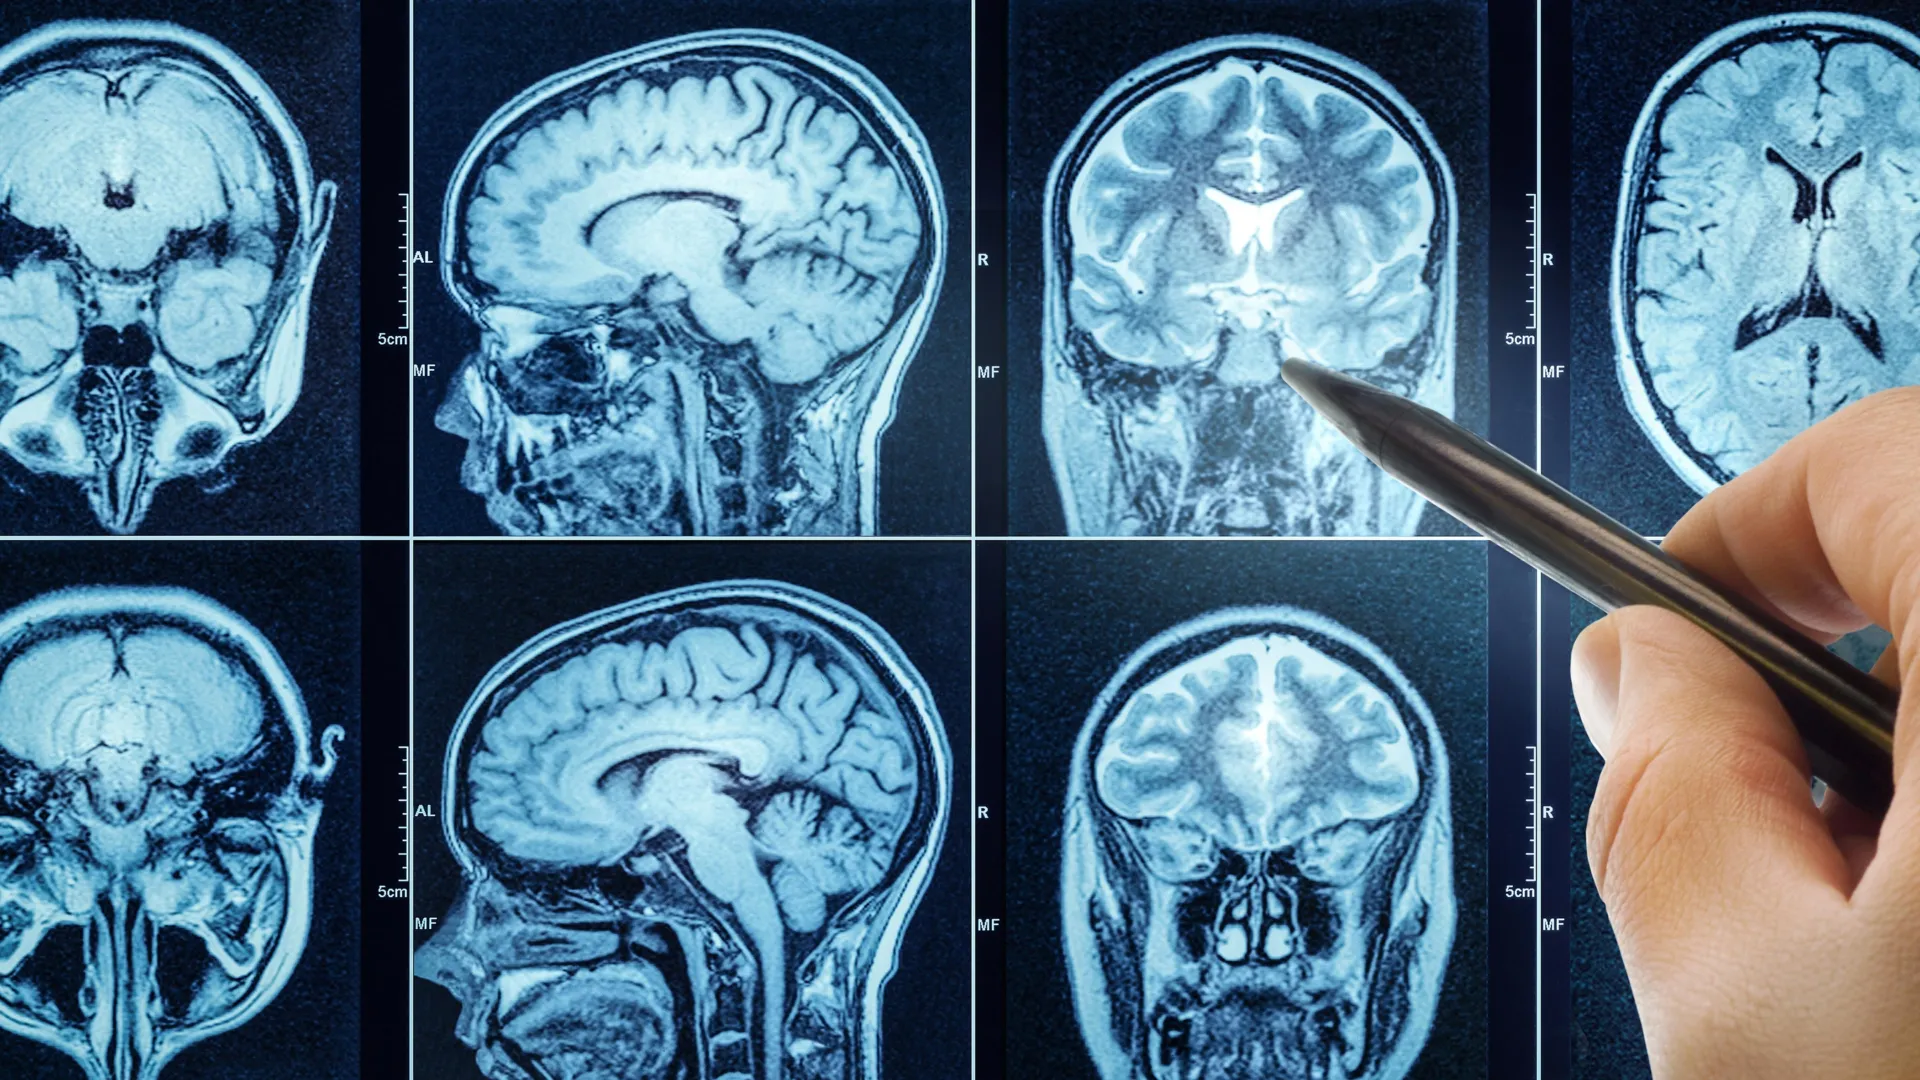

About nine years after the initial sleep assessment, researchers scanned all these participants' brains with MRI. But here's where it gets sophisticated. They didn't just look at brain scans visually. They used machine learning models—AI trained on thousands of brain scans—to estimate each person's biological brain age. Think of it like a model that's learned the patterns of how brains actually age, then applies that knowledge to estimate where any individual brain falls on that aging timeline.

The brain aging findings from MRI aren't just statistical artifacts. Researchers can actually see physical differences in brains of people with poor sleep versus those with good sleep.

People with poor sleep show several structural differences:

Reduced Gray Matter Volume: Particularly in the hippocampus (crucial for memory), prefrontal cortex (decision-making and impulse control), and anterior cingulate cortex (emotion regulation). These regions are smaller, with fewer neurons.

White Matter Hyperintensities: Bright spots visible on MRI indicating damage to white matter—the brain's communication cables. These are associated with cognitive decline and dementia risk.

Reduced Cortical Thickness: The gray matter layer at the brain's surface is thinner, suggesting neuronal loss.

Impaired Connectivity: Brain regions that normally communicate well show reduced functional connectivity. It's like the brain's internal network is degrading.

Increased Ventricular Size: The fluid-filled chambers in the brain's center expand, a sign of brain tissue loss.

These aren't subtle changes. They're measurable, consistent, and associated with cognitive problems in real life. People showing these changes perform worse on memory tests, processing speed tests, and executive function tests.

The encouraging part: these changes appear to be at least partially reversible. When people improve their sleep, brain changes begin to normalize. This suggests that sleep deprivation causes damage, but not necessarily permanent, irreversible damage—if addressed.